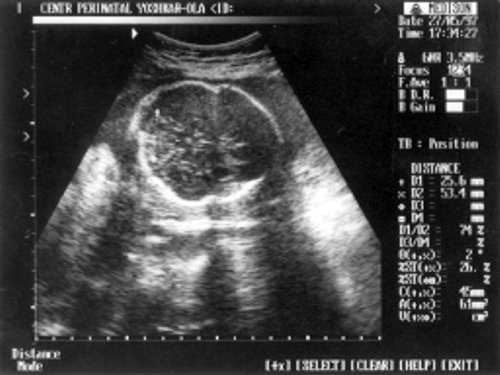

При ультразвуковом исследовании обнаружено: 1 живой плод в головном предлежании.

Данные фетометрии:

- (бипатериальный размер головы - от виска до виска) = 65 мм - 26 нед.,

- ОкГ (окружность головы) = 244 - 26 нед. + 3 дня.

- МРМ (межполушарный размер мозжечка) = 25,6 мм - 23,5-24 нед. (рис. 1)

- ОкГрК (окружность грудной клетки) = 42 мм - 19,5 нед.

- ОЖ (окружность живота) = 182 мм - 22 нед. + 6 дн.

- ДБ (длина бедра) = 24 мм - 17 нед. (рис. 2)

- Плечевая кость = 16 мм - 14,5 нед. (рис. 3)

- Кости предплечья = 17,5 мм - 15,5 нед. (рис. 4)

- Малая берцовая кость = 22 мм - 18,5 нед.

- Большая берцовая кость = 24 мм - 18,5 нед.

Рис. 1. УЗИ плода - голова.